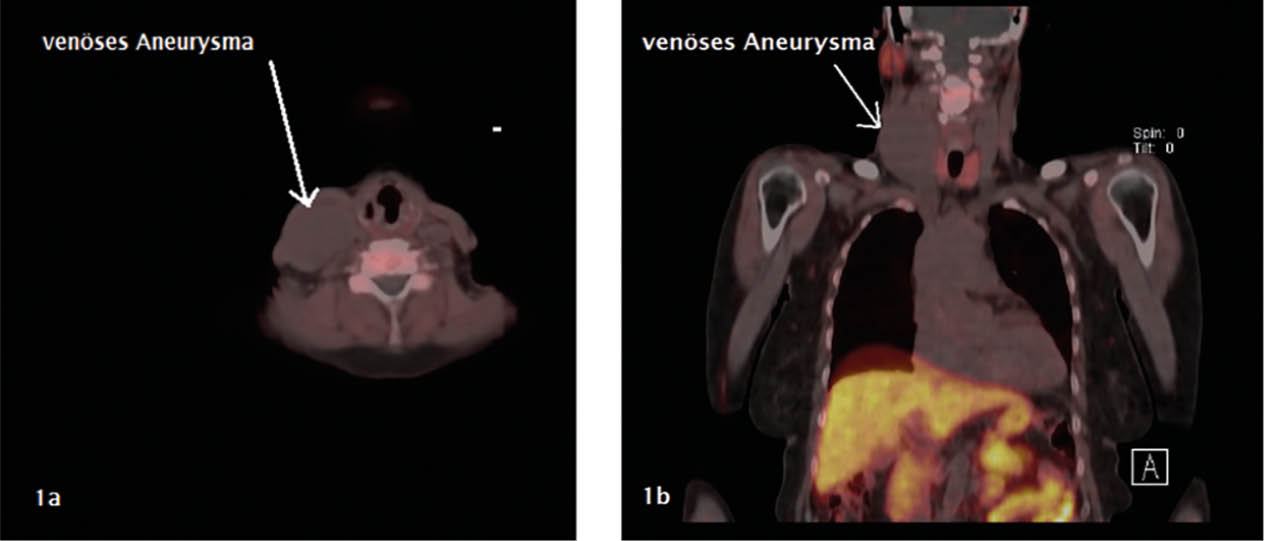

Aufgrund der symptomatischen Cholezystolithiasis nach stattgehabter akuter Cholezystitis wurde die Indikation zur elektiven laparoskopischen Cholezystektomie gestellt. An diagnostischen Verfahren wurden auswärts ein Angio-MRT (Abb. 1 – 4) des Oberbauches und eine Magnetresonanz-Cholangiopankreatikographie (MRCP) durchgeführt, welche eine Cholezystitis bei Cholezystolithiasis und eine beginnende Leberzirrhose nachweisen konnten. Im Rahmen der präoperativen Vorbereitung wurde eine Echokardiographie durchgeführt, in welchem eine Herzinsuffizienz infolge der Volumenbelastung durch die AV-Shunts i.R. des KMS und eine „Cirrhose cardiaque“ ausgeschlossen werden konnten. Als Marker einer intravasalen Gerinnungsaktivierung wurden erhöhte Prothrombinfragmente, D-Dimere und eine erniedrigte Antiplasmin-Konzentration sowie eine gesteigerte Fibrinolysekapazität detektiert. Eine sekundäre Thrombozytopenie oder eine Fibrinogen- und Faktor-XIII-Verminderung konnten ebenso wie das Vorliegen eines erworbenen von-Willebrand-Syndroms ausgeschlossen werden.

In einer hämostaseologischen Vorstellung wurde die Pausierung der Thrombozytenaggregationshemmung über 7 d unter „Bridging“ mittels niedermolekularem Heparin und eine medikamentöse Hemmung der Hyperfibrinolyse durch Tranexamsäure bis zum 3. postoperativen Tag bzw. in Abhängigkeit von Klinik und des hämostaseologischen perioperativen Monitorings empfohlen. Als perioperative Antibiotikaprophylaxe wurde Imipenem eingesetzt. Der Kameratrokar wurde entsprechend der aus dem Angio-MRT bekannten linksseitigen Ausprägung der Gefäßmalformationen (Abb. 1 – 4) in typischer Nabelposition platziert.

Abb. 1: Angio-MRT mit Transversalschnitt des oberen Abdomens auf Höhe der Gallenblase: Neben der hydroptisch geschwollenen und wandverdickten Gallenblase -> Hämangioendotheliom

im Bereich der ventralen und dorsalen linken Rumpfwand